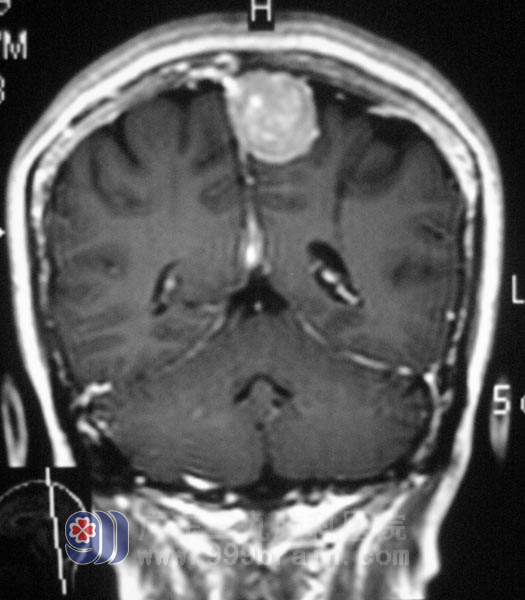

移居澳门已经多年的赵女士,退休后儿孙绕膝其乐融融。但在今年的春节期间,赵女士出现天旋地转般的头晕,伴有呕吐,家人以为是节日期间走亲访友劳累过度,加上菜肴油腻,出现呕吐,且天气寒冷,当地医院以感冒治疗后症状有所好转。一段时间后,赵女士的头晕症状再次出现,症状较前加重, CT检查提示左侧额顶部占位性病变。

广东三九脑科医院 综合神经外科 鲁明主任看过检查资料后告诉家属:肿瘤生长在语言和运动的功能区内,手术有可能会影响到语言、肢体功能,且肿瘤血供比较丰富,术后可能会现颅内出血;心电图检查提示T波异常,经会诊后认为赵女士心脏可以耐受手术。

4月19日,由鲁明主任主刀,在全麻下为赵女士行左侧额顶镰窦旁占位性病变切除+颅内压探头置入术,导航定位,术中可见肿瘤侵袭硬膜,近矢状窦硬膜破坏,肿瘤深入窦内,肿瘤基底部位于矢状窦内,显微镜下全切除肿瘤。

术前担心的情况术后都没有发生,赵女士肢体活动、语言功能都保存完好,术后病理结果为:(左额顶)纤维型脑膜瘤,WHO I级。现已康复出院。

▲手术前